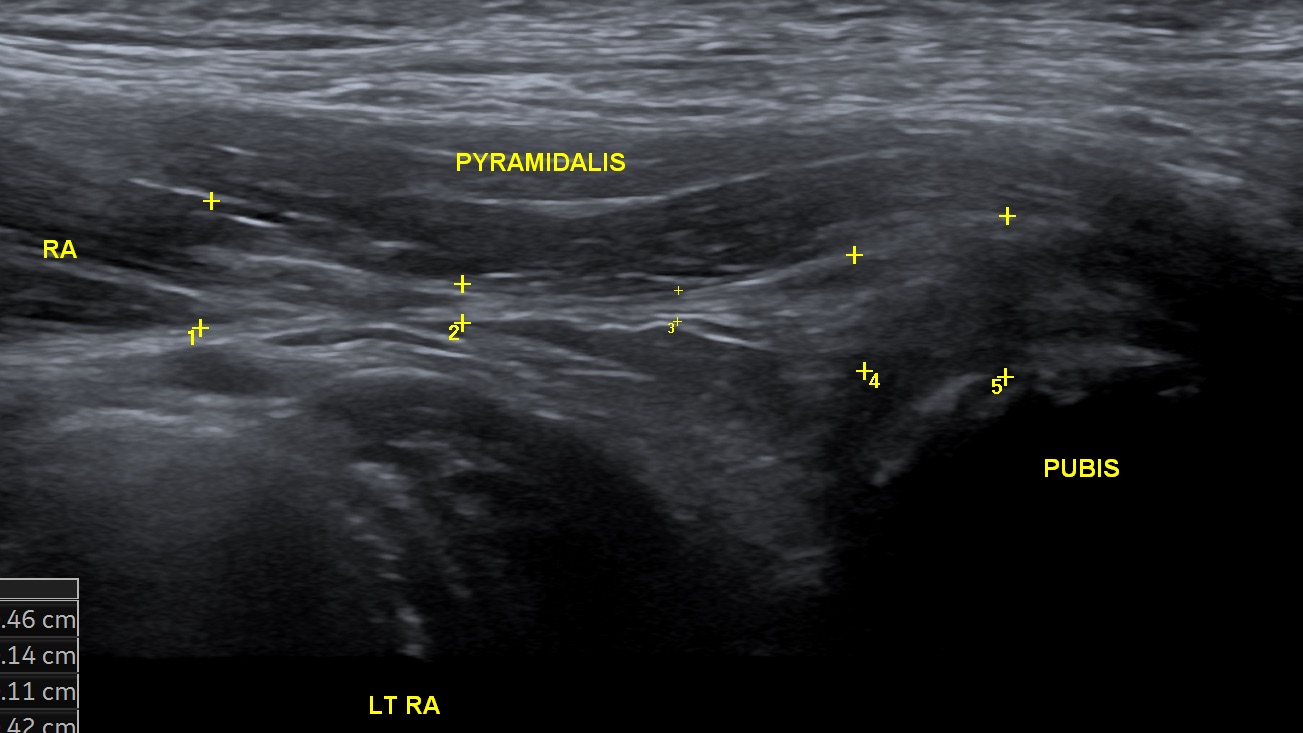

Rectus Abdominis

• Proximal rectus femoris assessment.

• Conjoint tendon injuries - how to recognise and evaluate with ultrasound.